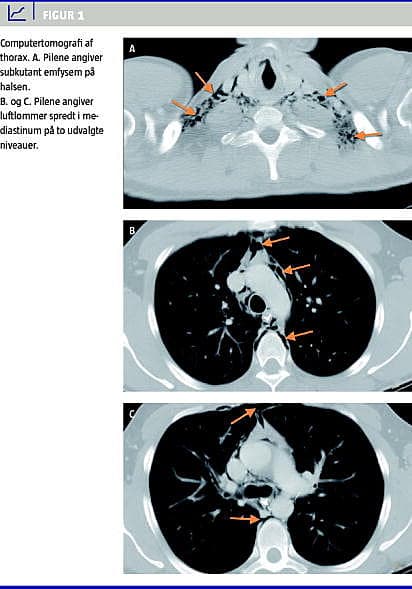

Paraklinisk var der normale koronarenzymer og marginalt forhøjede infektionstal. Et elektrokardiogram (ekg) viste sinusrytme uden tegn til iskæmi. Røntgen af thorax viste luft i mediastinum og subkutant emfysem på halsen, men ingen pneumothorax. En computertomografi (CT) med kontraststof af øsofagus viste ingen tegn på lækage. Man genfandt emfysem i mediastinum og subkutant på halsen (Figur 1 ).